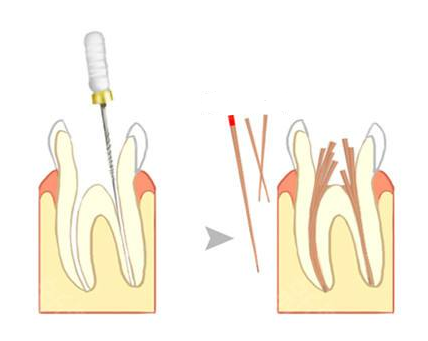

虽然根管治疗已经是一种非常广泛的治疗方式,但是它的治疗难度是非常高的,我们的牙齿内部结构,并不是像我们肉眼看到这么简单的,特别是根管治疗进行的位置——牙根,这里的结构精细而复杂,有的根管还呈现网眼一般的,因此根管治疗难度系数是至高的,对医生的技术以及治疗设备要求是非常高的,可以说“细节决定成败”只要在治疗过程中,一个小小的细节没有注意到,就会导致根管治疗失败。

例如我们的磨牙是很容易发生蛀牙的,一旦蛀牙没有及时治疗,就会引发牙髓炎,所以这颗牙齿进行占很大比例,同时它的治疗难度是至高的,因为患者嘴巴张开是有极限,越往里面的磨牙,医生的视线越受到影响,就会导致无法直接看到牙根内部,特别一些小诊所不具备专业设备,只能靠医生的触觉、普通的设备完成治疗,是很容易出现根管清除不完全、根管欠填这些都会导致根管治疗失败!而惠安齿科引进的德系全智能专业根管治疗设备,和根管名医坐诊使根管治疗得到大大的保障。